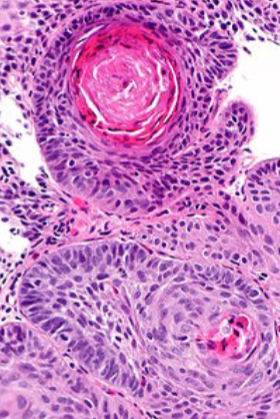

Squamous Carcinoma

Arise from squamous dysplasia

Squamous: squamous pearls